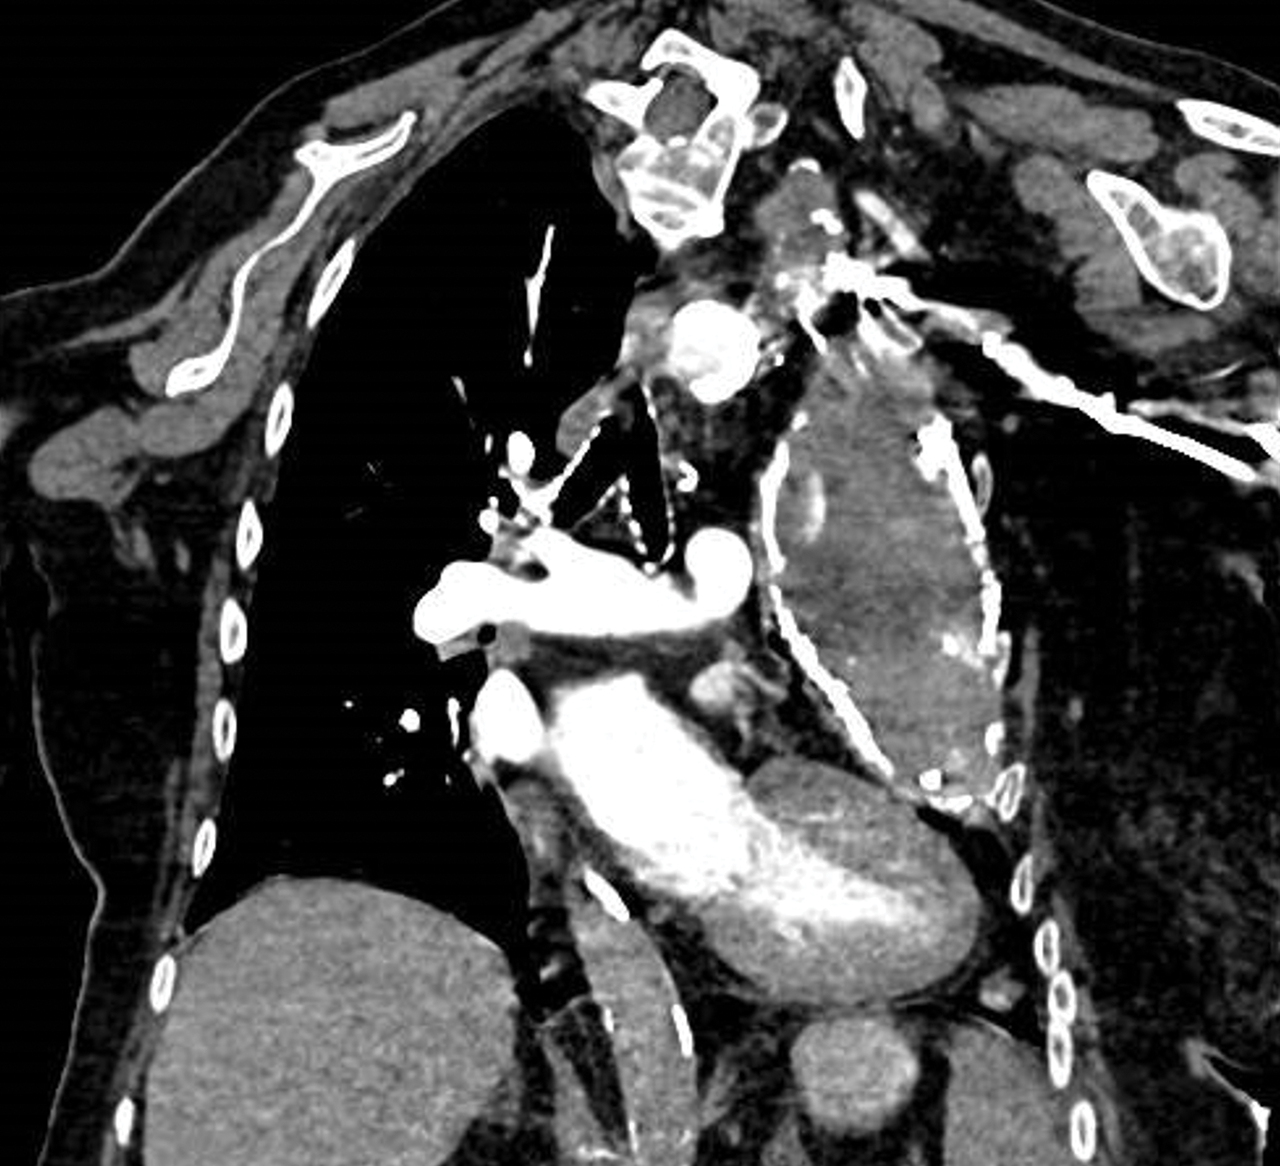

Les séquelles pleurales à type de calcifications (aspect en « os de seiche ») sont la conséquence de l’absence d’un traitement bien conduit.